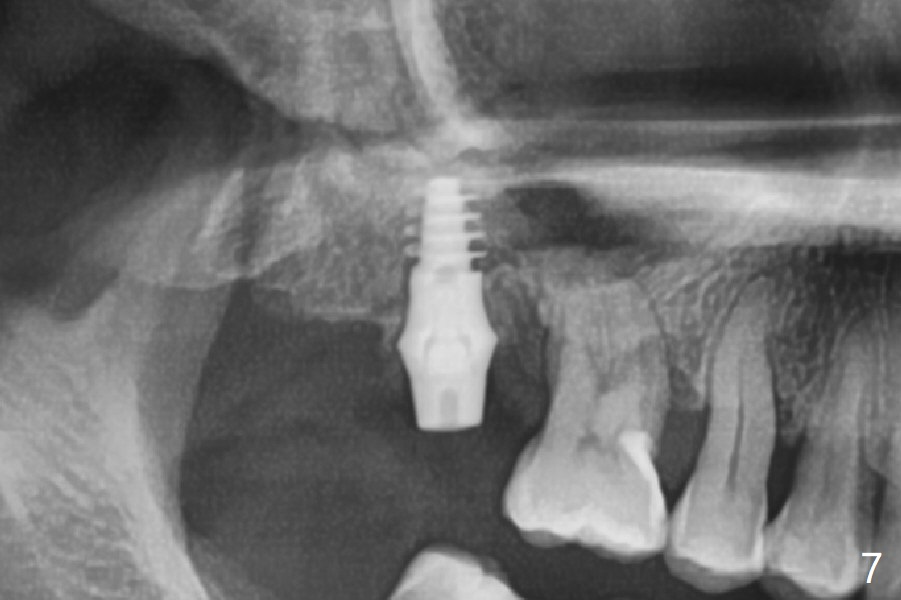

After extraction of the tooth #2 (Fig.1), osteotomy is supposed to be initiated in the mesial slope (Fig.2 arrow). With Magic Expanders (3-4.8 mm), osteotomy ends up in the bottom of the socket (Fig.3). Trajectory is found to be off when 4x9 and 5x9 mm dummy FC implants are placed with stability (Fig.4,5). The final implant, Magicore (5x7(3)mm, >29 Ncm), appears to be placed too deep for restoration (Fig.6,7); a screw retained crown may be a solution. PRF membrane and Vanilla (allograft) are used for sinus lift (no sinus membrane perforation). Following Vanilla graft in the socket gap (Fig.6 *), another piece of PRF membrane is used to cover socket opening. The membrane is fixed in place with suture and periodontal dressing. The implant seems to have osteointegrated 3.5 months postop (Fig.8). After change to 4.3x5 mm solid abutment and mesial surface adjustment, impression is taken for early loading because of removal of #14 implant. In fact the patient is satisfied with mastication improvement at #2 later on.